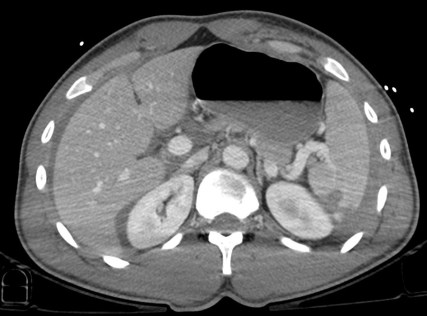

Varón jóven que acude a urgencias tras accidente de moto. Presenta dolor acusado en flanco izquierdo.

TA: 80 / 50 ; FC 110 lpm; Sat O2 93%.

Analítica: Discreta anemia.

Ante estos hallazgos, estamos ante un traumatismo esplénico grado III. Con la edad del paciente y los indicios de inestabilidad hemodinámica, se decidió tratamiento mediante embolización arterial.

- Laceración: líneas hipodensas e irregulares.

- Hematomas: áreas hipodensas focales en el interior del parénquima realzado.

- Hematomas subcapsulares: areas de baja densidad de morfología elíptica entre la cápsula esplénica y el parénquima realzado, la cual produce una marca o efecto de masa en el margen esplénico. El sangrado libre en el peritoneo no produce este efecto.

- Hemorragía activa: áreas de alta densidad (80 – 95 UH) por extravasación de material de contraste que aumenta con el tiempo. Es un indicador de fallo del tratamiento conservador.